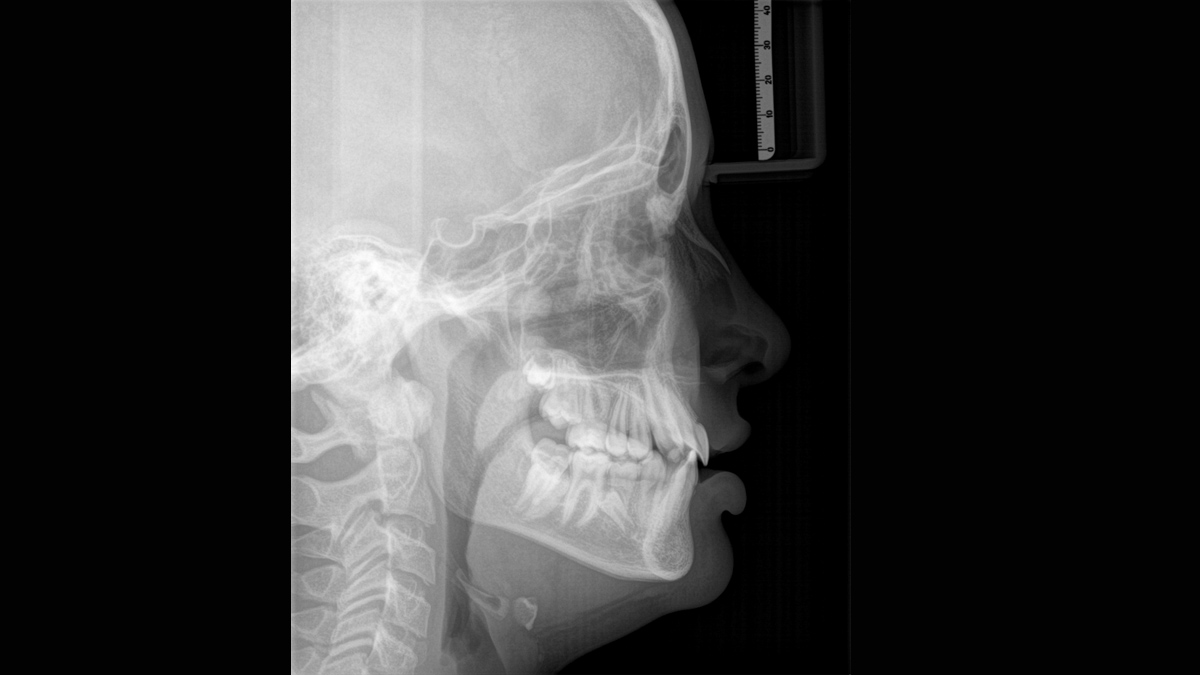

Imagen cefalométrica

Orthophos SL 3D ofrece la posibilidad de instalar un brazo cefalométrico en cualquier momento. Para asegurarse de que se ajusta a su sala de rayos X, el brazo puede montarse en el lado derecho o el lado izquierdo de la unidad.

Programas cefalométricos que cubren todas las necesidades ortodóncicas

Usando un sensor específico, obtiene imágenes laterales y simétricas, así como imágenes del carpo. En casos de dientes desplazados, podría recurrrir a los beneficios de las radiografías en 3D para determinar la localización exacta.